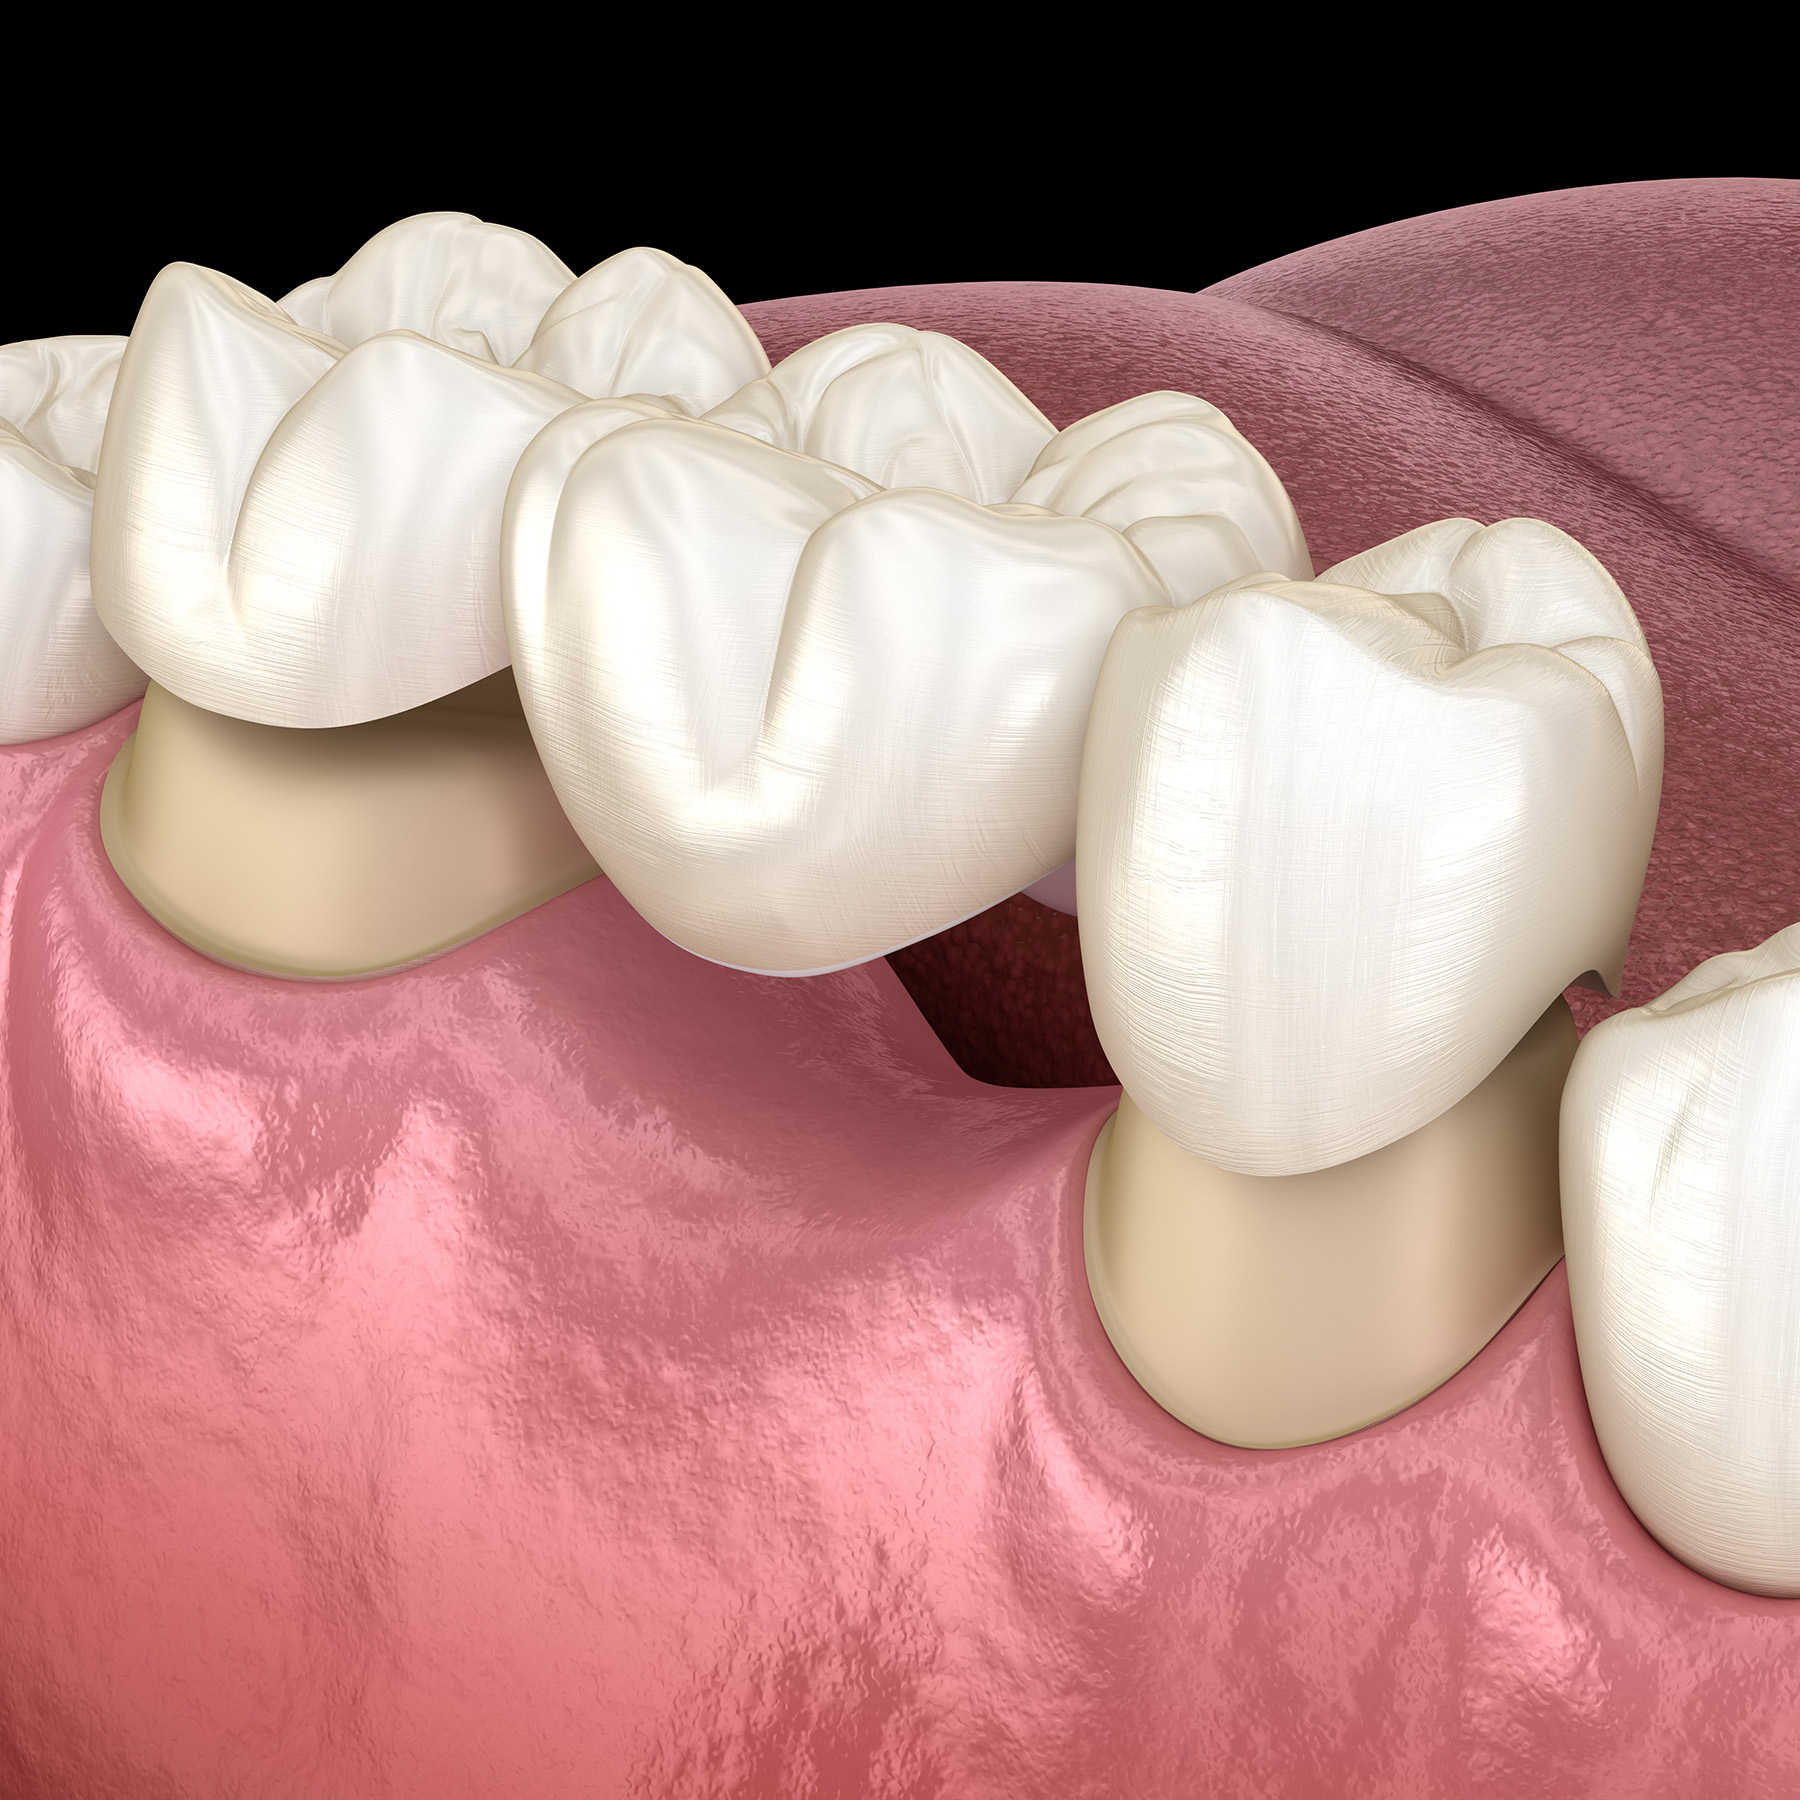

Dental crowns have evolved from simple protective caps to sophisticated restorations that blend form and function. Today's crowns, made from advanced materials like zirconia and lithium disilicate, offer unmatched durability and aesthetics. They not only protect damaged teeth but also enhance smiles through precise color matching and detailed surface textures. With innovations in digital imaging and CAD/CAM technology, the process of receiving a dental crown has become more efficient and comfortable than ever.

Dental bridges offer a reliable solution for missing teeth, restoring both function and aesthetics. At Royal Dental Center, these restorations are crafted using high-quality materials like ceramics and zirconia, ensuring durability and a natural appearance. The process involves precision engineering tailored to individual needs, from initial consultation to aftercare, making dental bridges an attractive option for comprehensive restorative care.